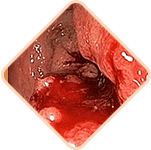

Gemorroyning 3 ta jiddiy xavfi

Quyidagi hodisalarning biron

biri halokatli bo'lishi mumkin:

Gemorroyda kengaygan qon tomirlari shikastlanishi va yorilishi mumkin, bu qon ketish xavfini oshiradi. Qon ketishining og'irligi yengildan og'irgacha o'zgarishi mumkin, bu jarrohlik aralashuvini yoki hatto qon quyishni talab qiladi.

Surunkali gemorroy qon tomirlarida qon quyqalarining paydo bo'lishiga olib kelishi mumkin. Vaqt o'tishi bilan bu qon quyqalari boshqa ichki organlarning tomirlarini sindirib, to'sib qo'yishi mumkin, bu yesa qon tomirlari, o'pka emboliyasi va koronar tromboemboliyani keltirib chiqaradi.